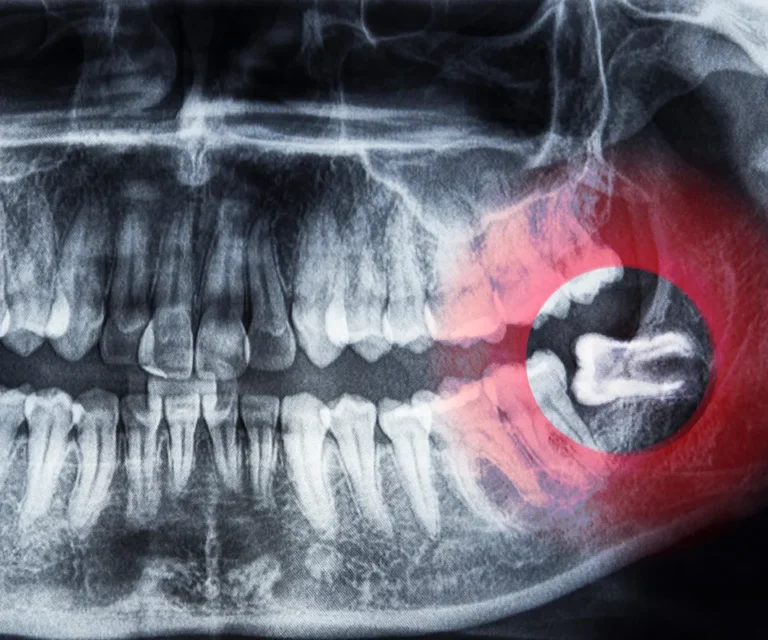

Wisdom Tooth Infection Emergencies

Wisdom teeth are especially prone to infection due to their position in the back of your mouth, making them harder to clean. Common signs of a wisdom tooth infection include:

- Gum swelling around the wisdom tooth

- Difficulty opening your mouth

- Pain radiating to your ear or jaw

- Red, inflamed gum tissue

- Bad breath or unpleasant taste

Our emergency dentists in Peoria can assess whether you need antibiotics, drainage, or immediate extraction to eliminate infection and pain.